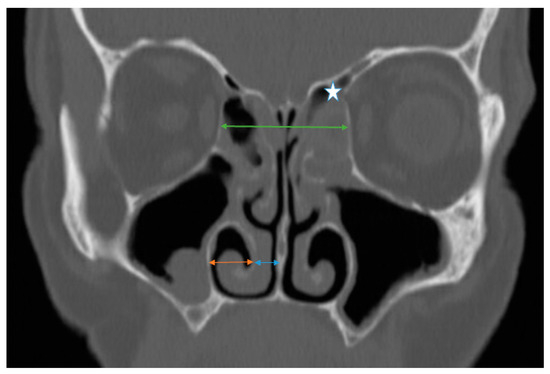

To assess the radiological position of the inferior turbinate, several measurements were performed bilaterally using the CT scan (coronal plane). These measurements comprised the following: 1. The horizontal distance between the lateral border of the IT bone and the lateral nasal wall (ITL). 2. The distance between the medial border of the IT bone to the median nasal line (vertical line from the crista galli to the nasal spine) (ITM) (Figure 1). The point of entry of the anterior ethmoidal artery into the nasal cavity (nipple sign) served as an anchoring point to produce reproducible and accurate measurements in both the baseline and post-ESS CT images.

To investigate the effect of ethmoidectomy on the LP position we performed several measurements: in the coronal plane, a vertical line was drawn from the crista galli to the nasal floor, then a perpendicular line was drawn from one lamina papyracea reaching the contralateral lamina passing through the nasal septum at the level of the cribriform plate. The distance between the two laminae on the coronal CT scan was defined as the interorbital distance (IODcoronal). The point of entry of the anterior ethmoidal artery into the nasal cavity (nipple sign) served as an anchoring point to produce reproducible and accurate measurements in both the baseline and post-ESS CT images (Figure 1).

Figure 1. Sinus computed tomography scan, coronal plane. Star: the left anterior ethmoid artery. Green line: IOD in the coronal plane (IODCoronal). Orange line: distance between the lateral border of the inferior turbinate to the lateral nasal wall (ITL). Blue line: distance between the medial border of the inferior turbinate and the septum.